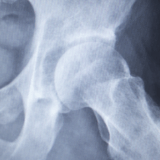

人工股関節置換術(THA)は変形性股関節症や大腿骨頭壊死などによる強い痛みに対して生活の質を高めるために行われる治療です。